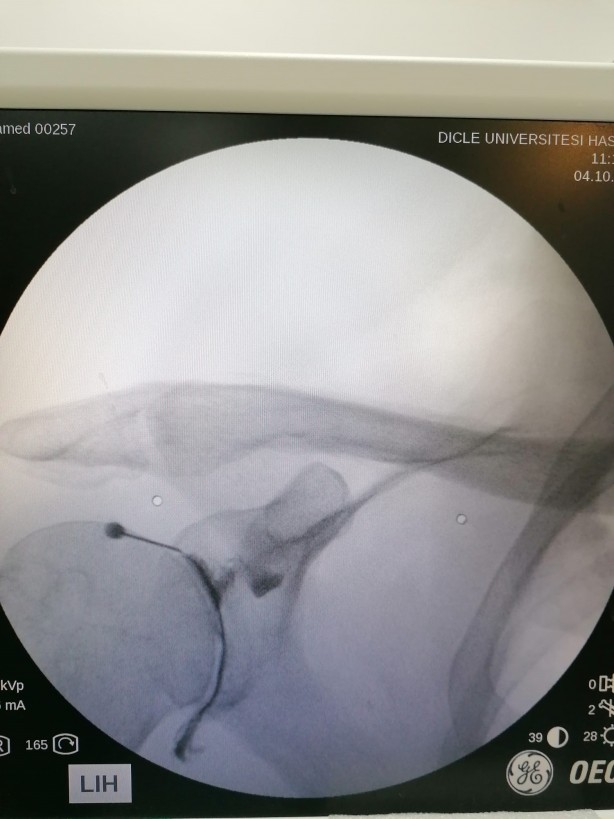

Kök tedavisinin görüntüleme eşliğinde yapılması gerektiğine dikkat çeken Karaman, şunları kaydetti: “Kök hücre tedavisi, körlemesine yapılan bir tedavi değildir. Mutlaka görüntüleme eşliğinde yapılıyor. Hastamıza tedavi uygularken floroskop cihazını kullanmaktayız. Uygulama anına geldiğimiz zaman hastanın ilgili bölgesinin tam olarak görüntüsünü görmekteyiz. Burada birebir koordineli bir şekilde özel iğne şeklinde olan elektrodumuz var. Onunla beraber ekrandan göre göre ilerletiyoruz. Daha sonra doğrulamak için yerimizi boya veriyoruz. Dağılımı gördükten sonra hastamıza kök hücreyi verip işlemimizi tamamlamış oluyoruz.”